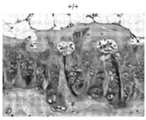

도 3a 및 도 3b는 야생형(도 3a) 및 동형접합체 녹아웃(도 3b) 마우스 유래의 헤마톡실린 및 에오신 염색된 대퇴부 연골의 대표 절편의 광학 현미경 이미지를 보여준다.